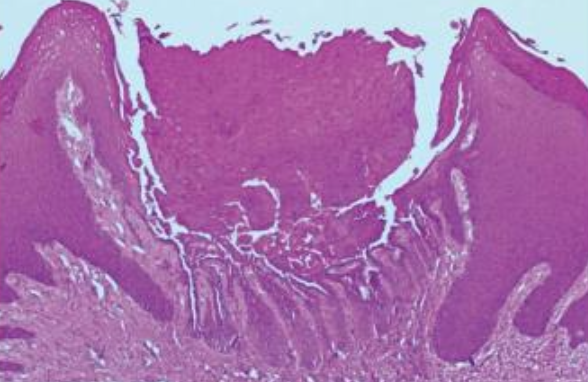

alt text alt text alt text

alt text

• 上皮內裂 (acantholysis)

• Rete ridges 窄長,且呈試管狀。

• 角化不良細胞: corps ronds & grains(類似於穀粒)

• central keratin plug : keratin 堆積